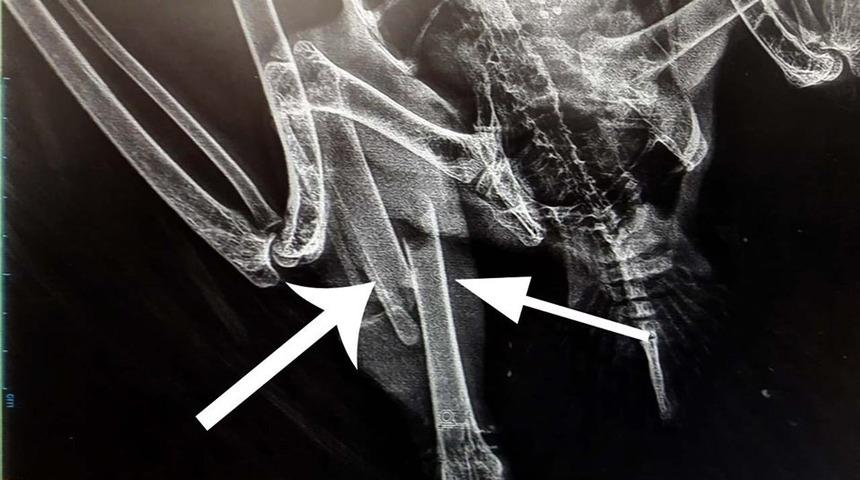

Iğdır’ın Tuzluca İlçesinde Mahmut Calayır tarafından yaralı halde bulunan akbaba Doğa Koruma ve Milli Parklar İl Şube Müdürlüğüne teslim edildi. Sağ bacağında sorun olmasından dolayı yeterli beslenemediği için yorgun düşen küçük akbaba’ya gerekli müdahale yapıldıktan sonra Kars Kafkas Üniversitesi Veterinerlik Fakültesi DKMP Yaban Hayatı Tedavi ve Rehabilitasyon Merkezine gönderildi. Çekilen röntgen sonucu "Tibia Kırığı" tespit edildi. Küçük Akbaba’nın ameliyata alınacağı öğrenildi.